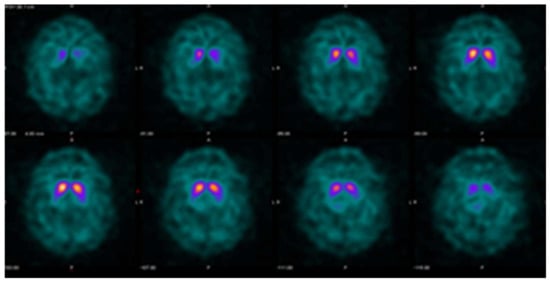

Figure 4.

Example DaTQUANT results in a non-PS patient demonstrating apparent loss of the normal “comma shape”, particularly on the right. However, none of the summary measures, SBR (1.23 to 1.33), z-score (−0.51 to −0.88), or percent deviations (−0.12 to −0.19) meet thresholds for abnormal. The caudate nuclei are noted to have relatively increased uptake (SBR 3.10–3.45, z-score 2.42–3.48) causing an apparent decrease in putaminal activity where there is none (“hot caudate” sign).